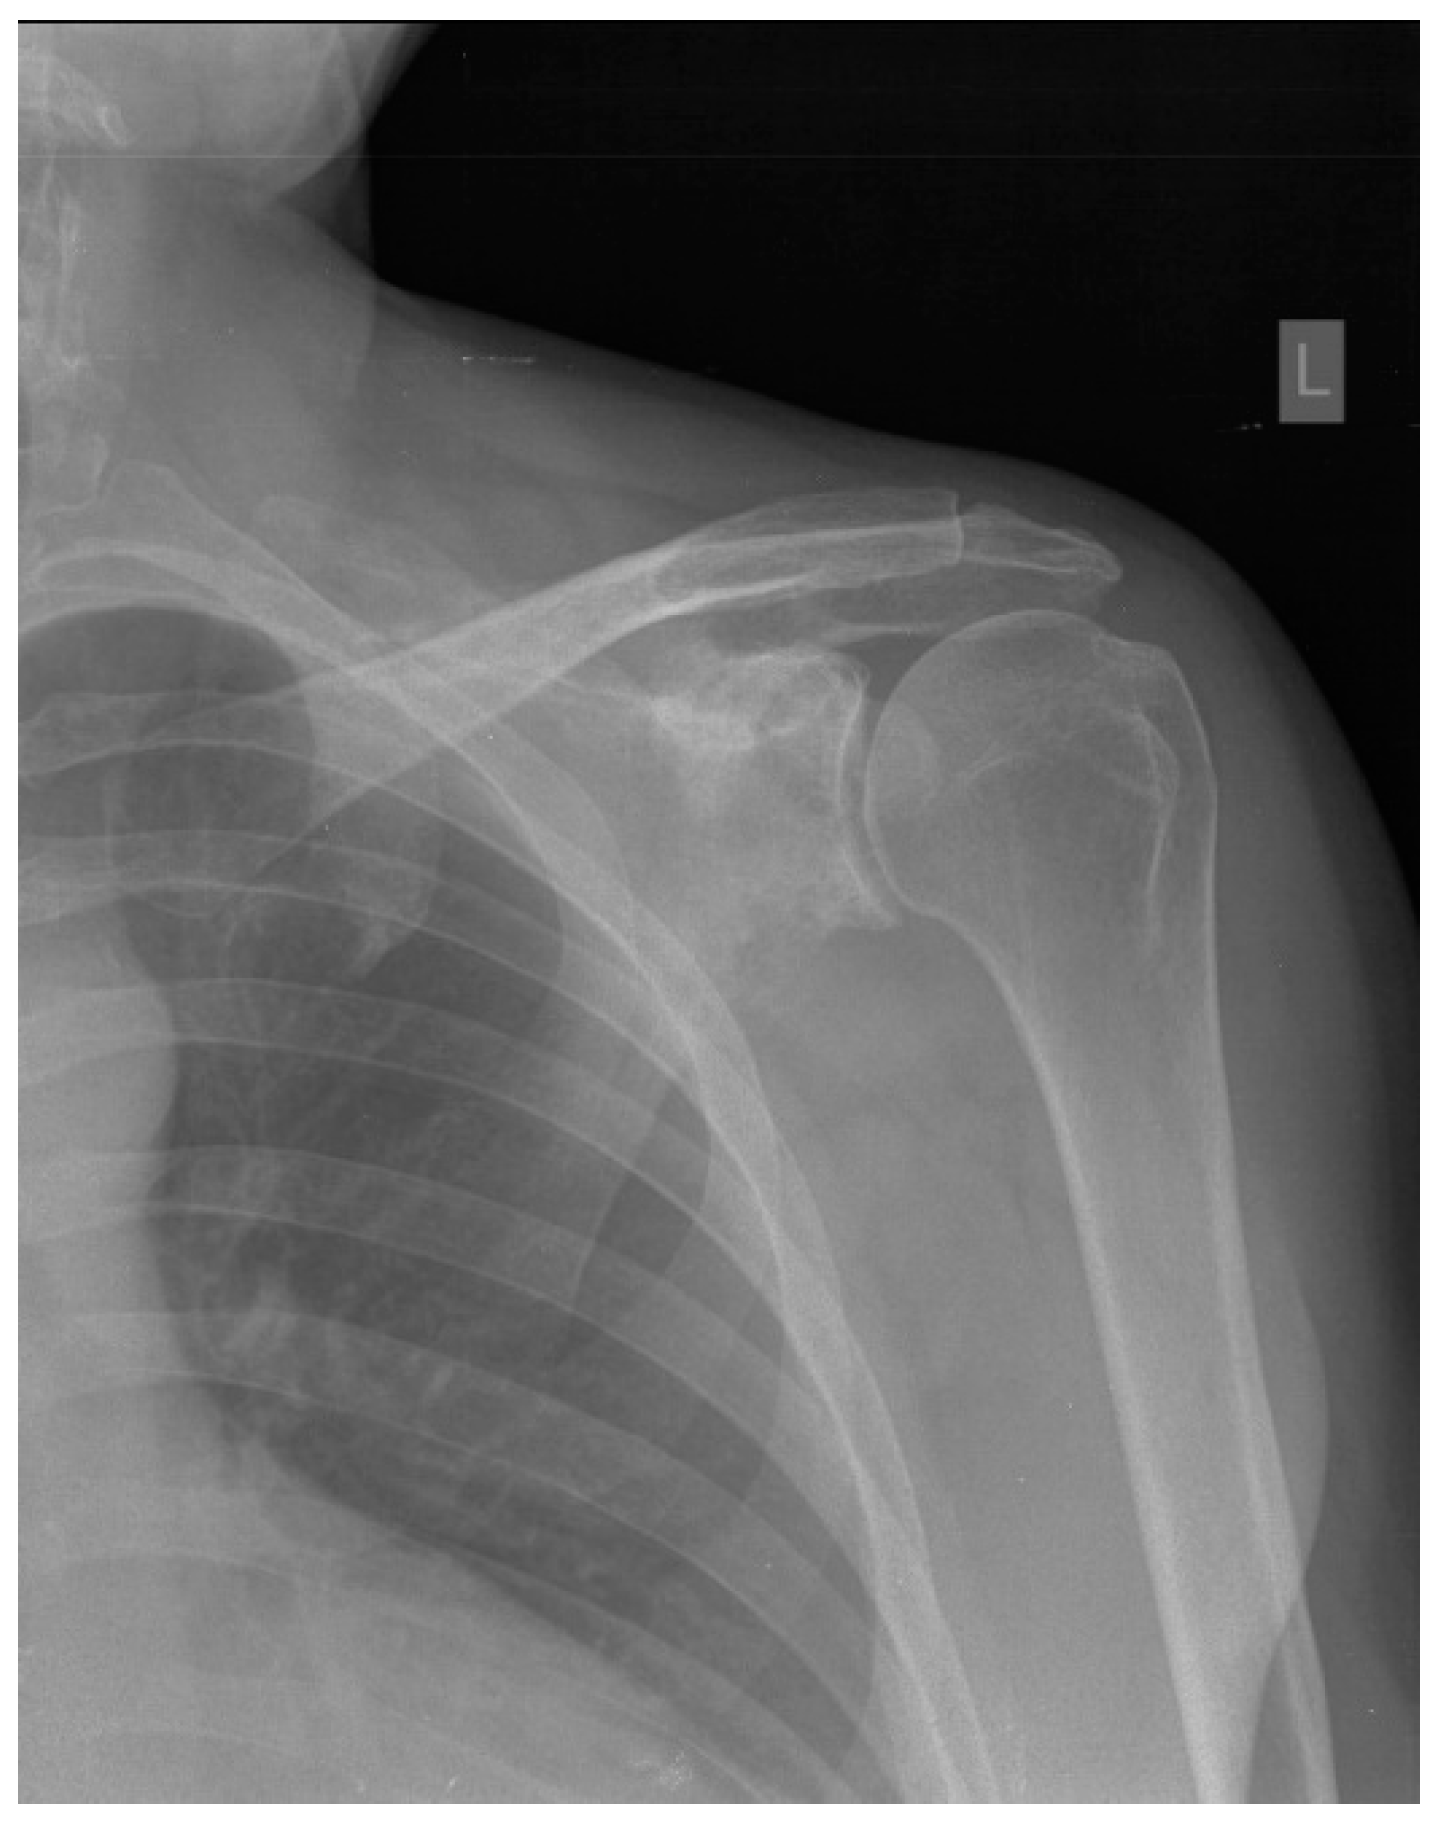

| Our patient | M/45y | Paresthesia, tingling, numbness and edema of the little and ring finger | Two years/ two years |

Surrounding soft tissue | R-CHOP chemotherapy + radiotherapy | Remission |